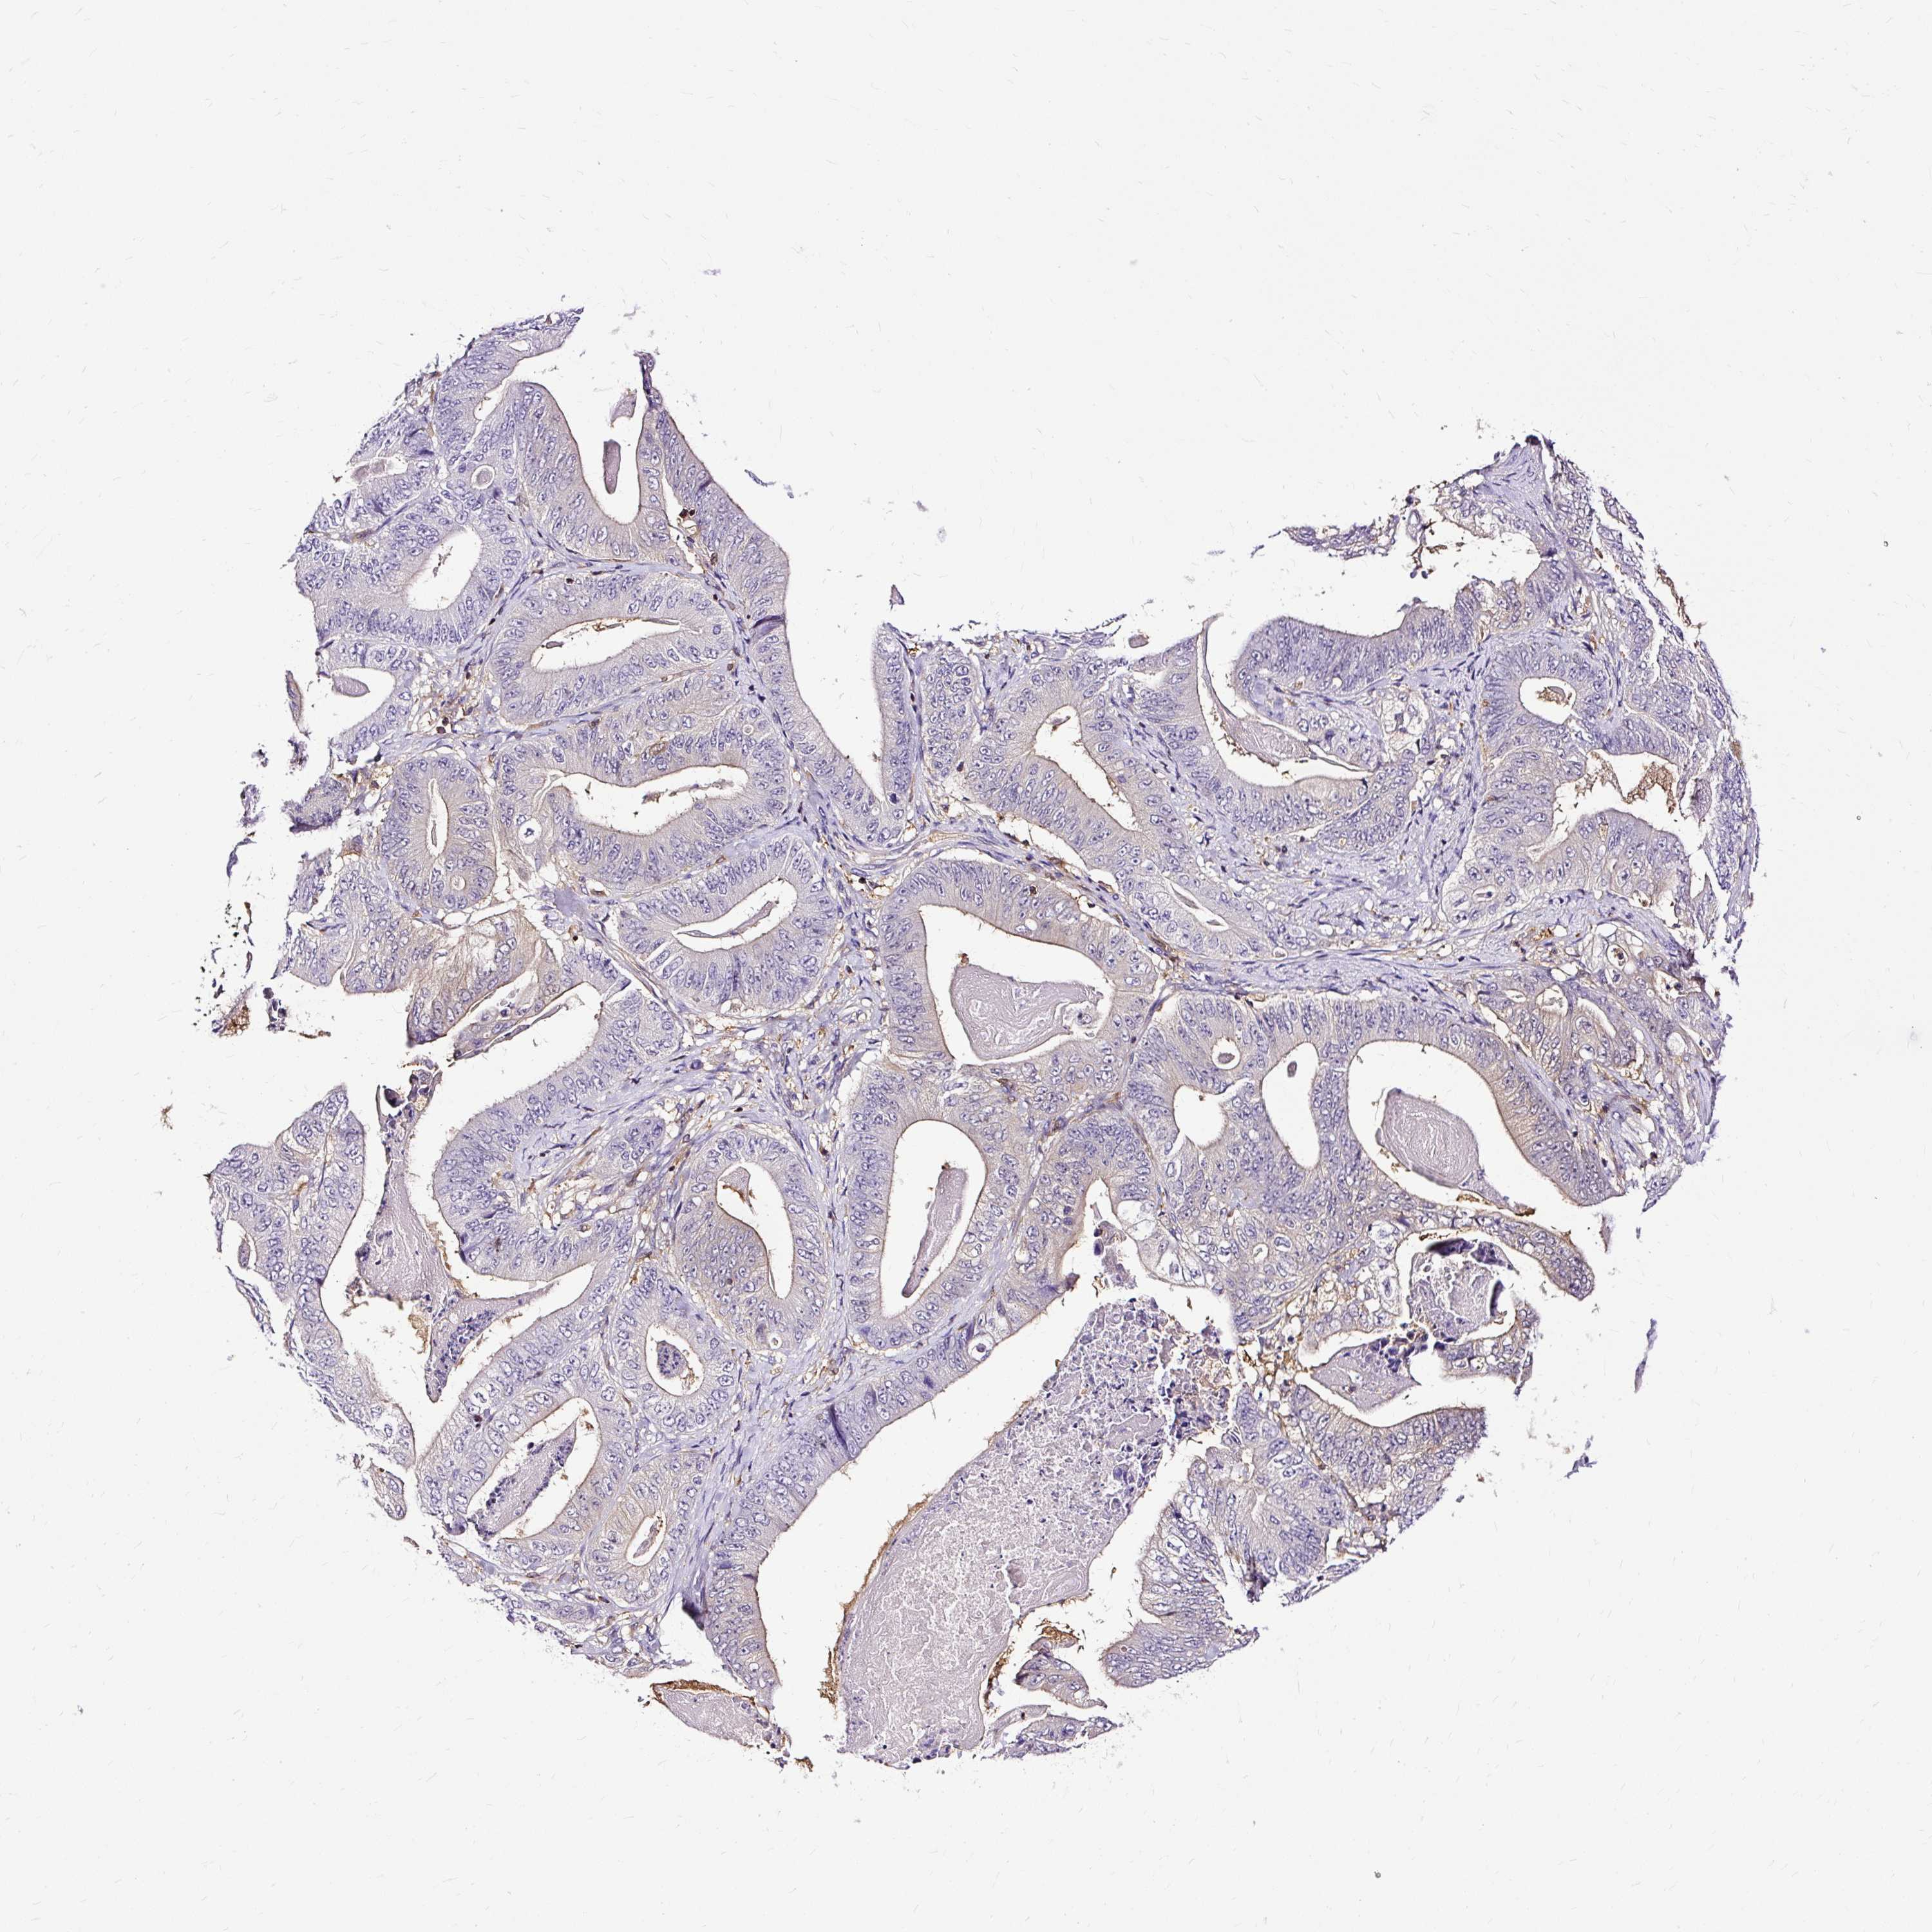

STOMACH CANCER - Protein expressioni

A mouse-over function shows sample information and annotation data. Click on an image to view it in a full screen mode. Samples can be filtered based on level of antibody staining by selecting one or several of the following categories: high, medium, low and not detected. The assay and annotation is described here.

Antibody stainingi

Antibody staining in the annotated cell types in the current human tissue is reported as not detected, low, medium, or high, based on conventional immunohistochemistry profiling in selected tissues. This score is based on the combination of the staining intensity and fraction of stained cells.

Each image is clickable and will lead to virtual microscopy that enables deeper exploration of all samples and also displays staining intensity scores, fraction scores and subcellular localization as well as patient and tissue information for each sample.

Antibody HPA053874

Staining

High

Medium

Low

Not detected

Intensity

Strong

Moderate

Weak

Negative

Quantity

>75%

75%-25%

<25%

None

Location

Nuclear

Cytoplasmic/membranous

Cytoplasmic/membranous,nuclear

Adenocarcinoma, NOS